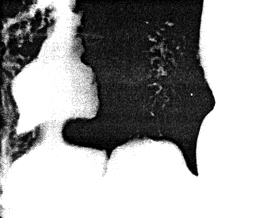

![]() |

| Fig. 13.3. Radiograph showing living anatomy. Two fine, flexible metal wires (retouched) are attached to serosal surfaces of lesser and greater curvatures. The space between the wires and intraluminal barium indicates the cylindrical muscular contraction |

Narrow, circumferential indentations of the barium column appeared in the body of the stomach and proceeded to move in a caudal direction. Opposite the indentations the fine, flexible wires remained in their original position, showing that these indentations were due to contraction waves in the walls and not "falling together" of the walls. At a point 3.0 to 4.0 cm orally to the pyloric ring each wave became stationary, at the same time initiating a concentric, cylindrical narrowing of the barium column in the remaining part of the stomach, as far as and including the area of the ring. Again the wires were seen to remain in their original position. During a contraction the space between the wires and the luminal barium widened to approximately 8.0 to 10.0 mm all round, indicating an active, tube-like or cylindrical contraction of the muscular walls, 3.0 to 4.0 cm in length (Fig. 13.3). After a second or two of maximal contraction, the walls relaxed and the cycle was repeated.